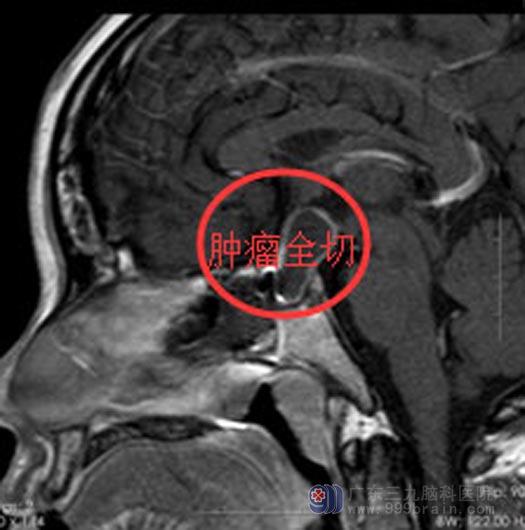

在广东三九脑科医院垂体瘤诊疗中心,由鲁明副院长主刀,实施“经鼻蝶鞍区占位切除术”,手术过程顺利。

▲手术后